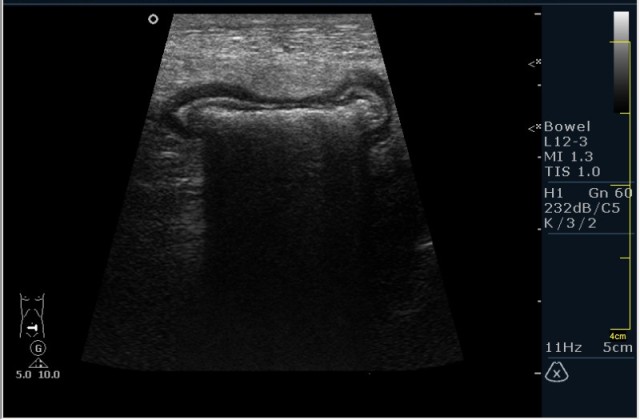

Пациент М. 60 лет с болями в левой подвздошной области. Пациент был направлен на УЗИ с диагнозом: левосторонняя почечная колика. Жалобы на боли в левой подвздошной области отдающие в таз. Анамнез без особонностей.

Пациента я сразу направил на эндоскопию. К сожалению, заключение было ожидаемым с моей стороны, опухоль (карцинома по результату биопсии).